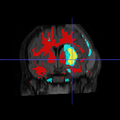

Image:New_data_p4_3.png|Segmentation result of a new subject (Y view)